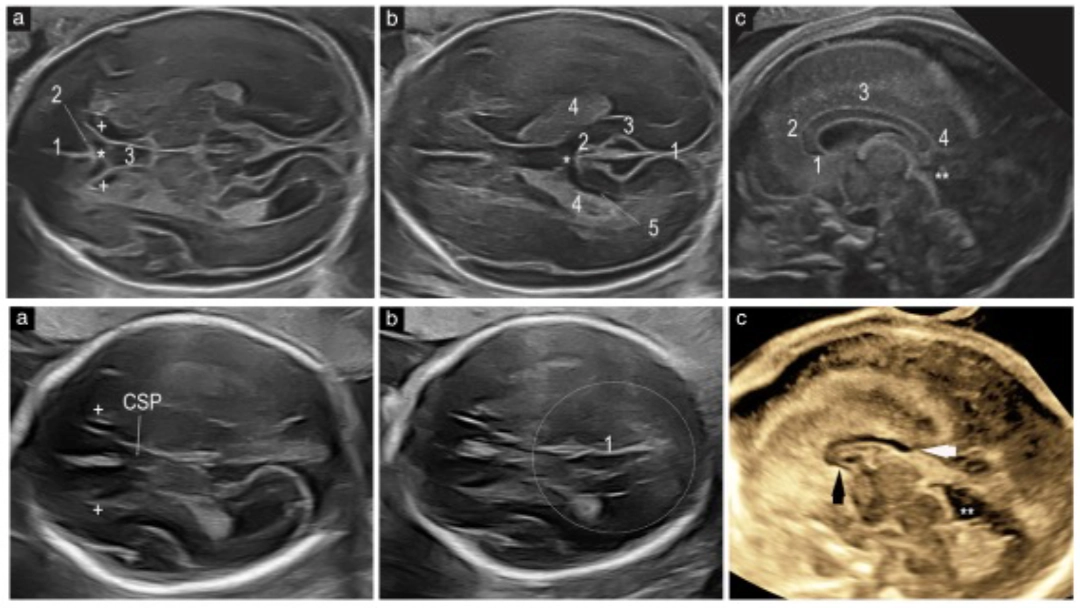

Ecografía transabdominal y transvaginal de un feto sano a las 22 semanas. Se observan estructuras normales del complejo anterior (CSP bien definido, astas anteriores con forma de coma) y del complejo posterior (surco calloso visible, CC cruzando la línea media). Fuente: Viñals et al., 2025.